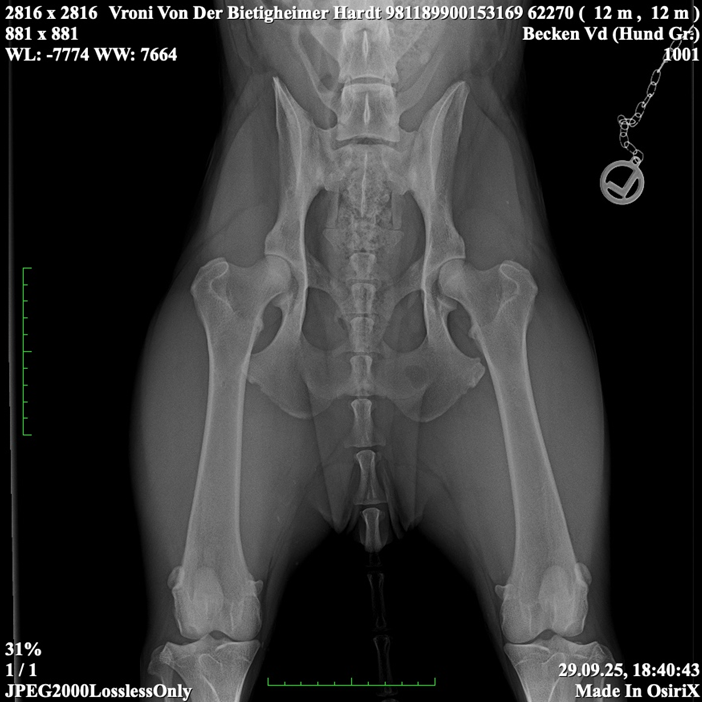

Vroni von der Bietigheimer Hardt

SZ. 2395403; WT: 27.09.2024;

HD ZW: kW25/02 „69“ Größen-ZW: kW25/02 „101!